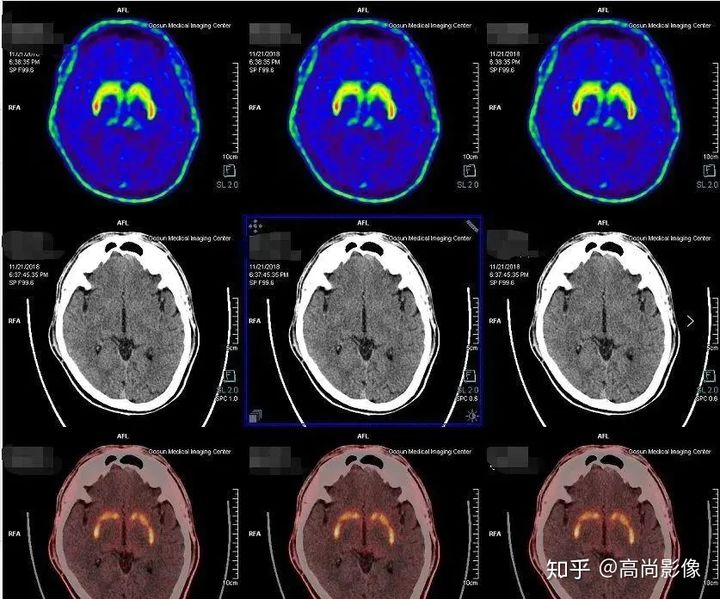

多巴胺轉(zhuǎn)運體顯像可以幫助鑒別診斷帕金森和良性震顫,具有良好的診斷效能。

1年多來,黃大爺?shù)碾p手總是抖個不停,他和家人都非常擔(dān)心。黃大爺來到中心進(jìn)行了PET/CT的檢查,檢查發(fā)現(xiàn),黃大爺?shù)亩喟桶忿D(zhuǎn)運體顯像基本正常,最后,黃大爺被診斷為良性震顫。

雙側(cè)尾狀核、殼核多巴胺轉(zhuǎn)運體分布對稱、均勻